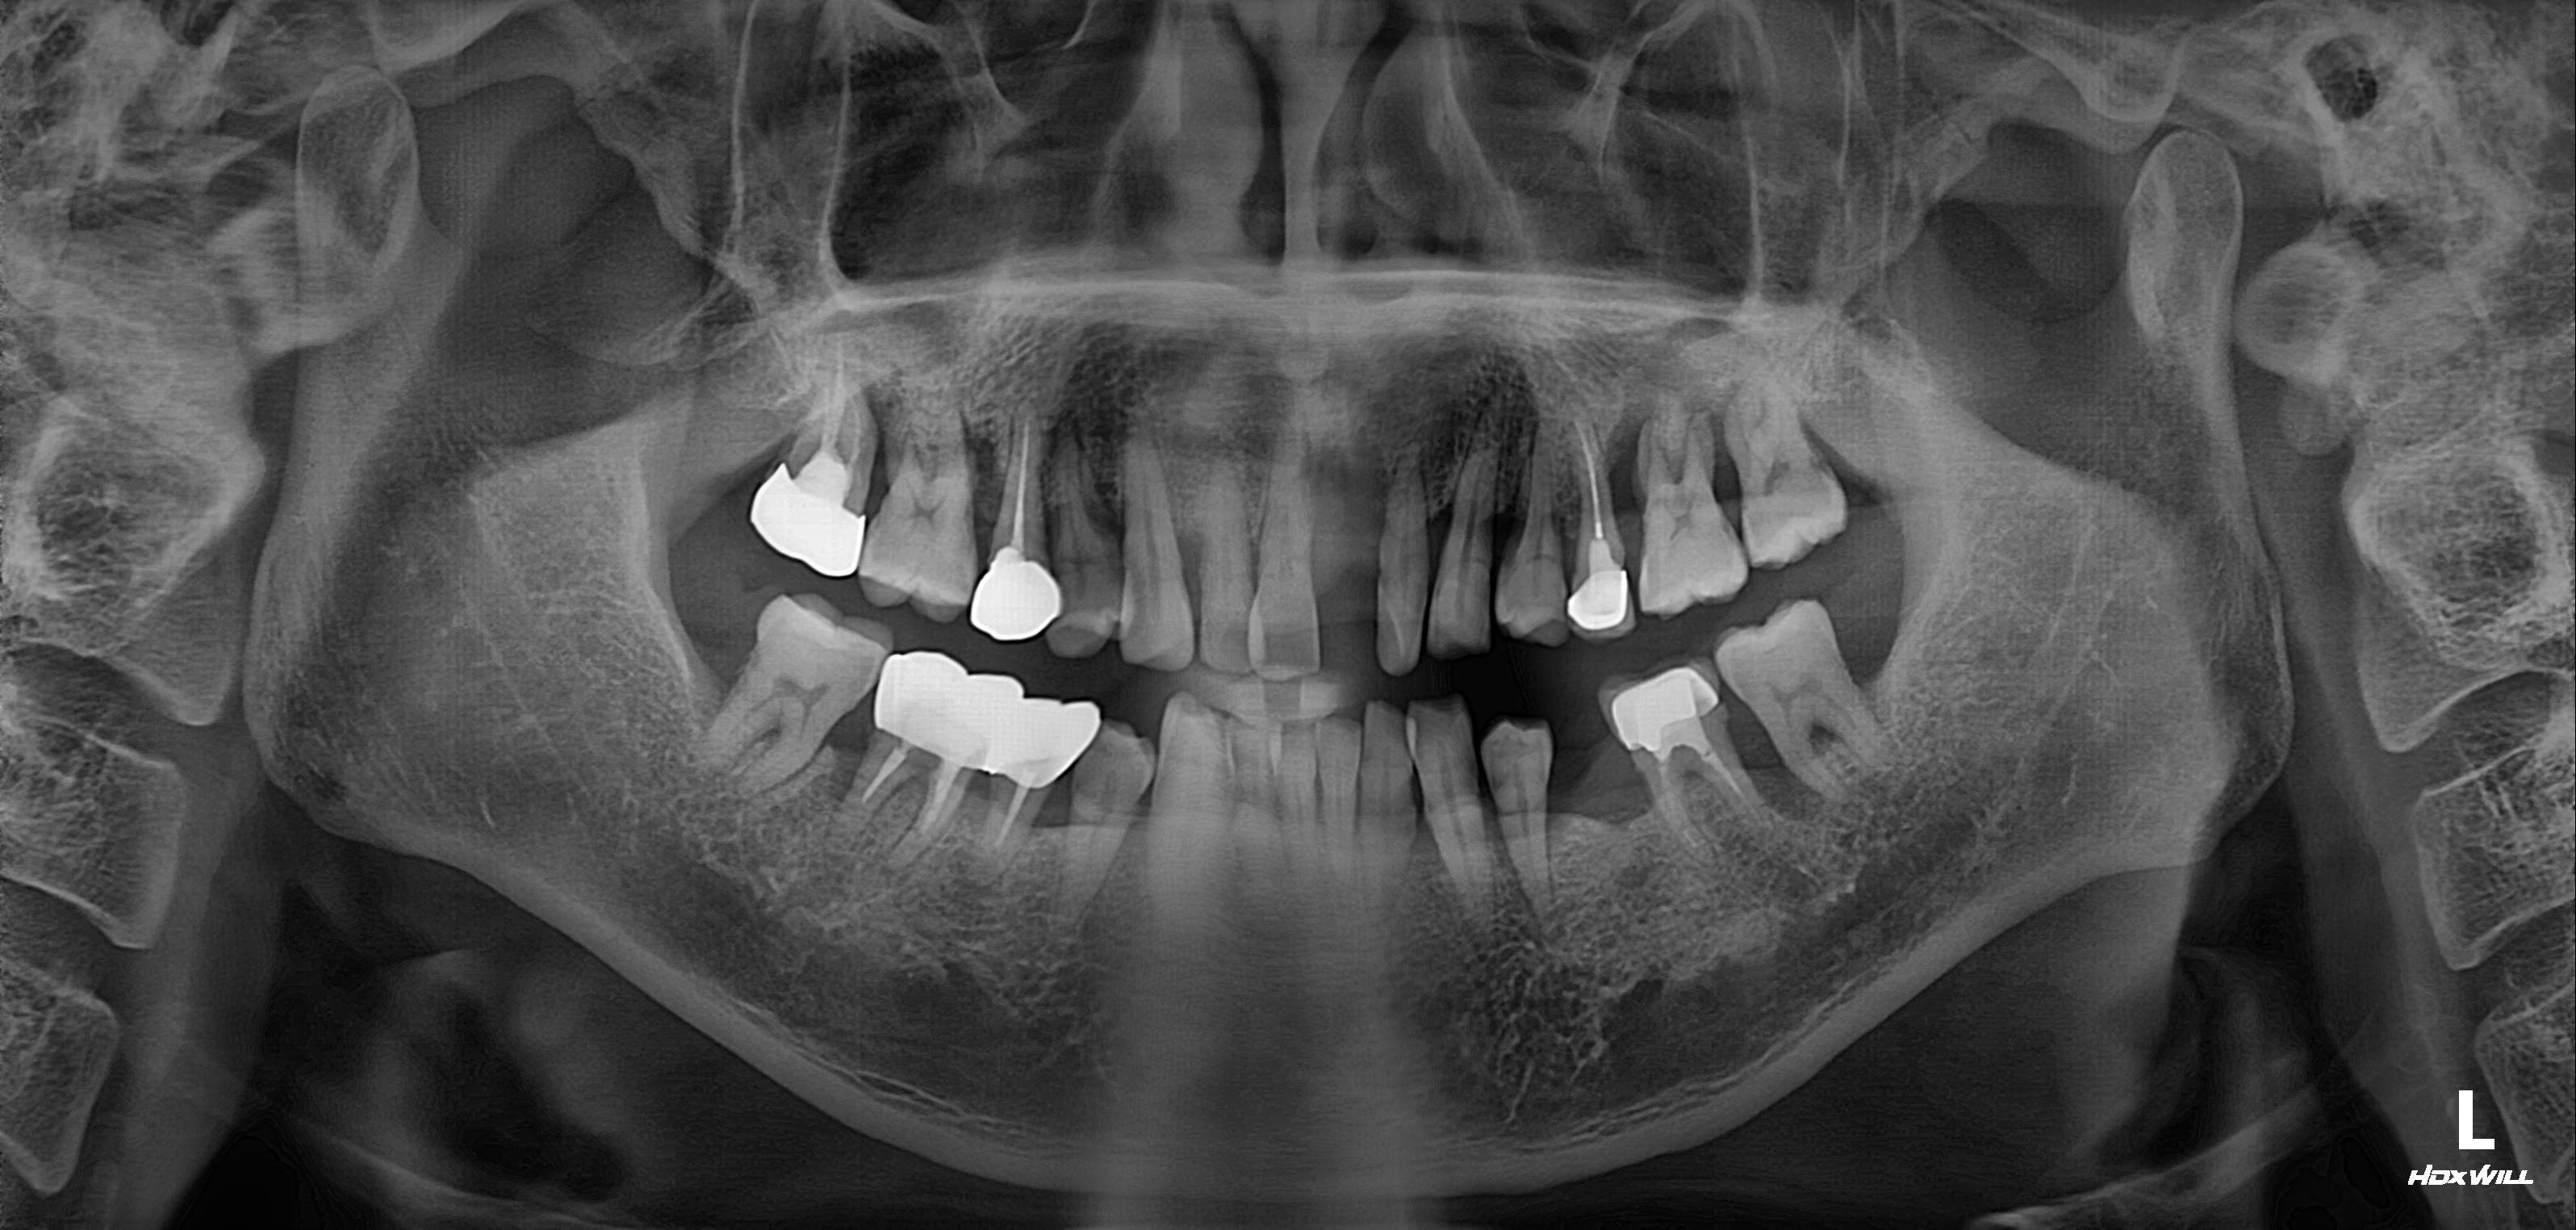

심미치료

전문가치아미백

전후사진